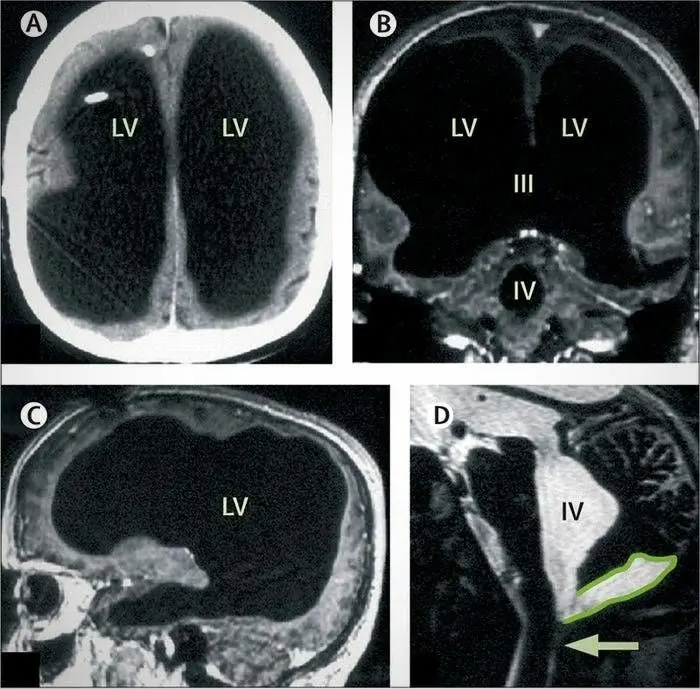

این مرد فرانسوی بعد از احساس ضعف در پای چپ خود و آن هم به مدت دو هفته، به بیمارستان مراجعه کرد. پزشکان بعد از اسکن مغزی او متوجه وجود یک محفظه پر از آب داخل مغزش شدند و به شدت از این قضیه شگفت زده شده بودند.

این اسکن ها نشان می داد که این مرد مغزی در سر خودش ندارد؛ در حالی که مایع مغزی نخاعی به شکل طبیعی در سر او جریان دارد اما از یک قسمت خورده می شود و به دلیل اینکه این مایع وارد سیستم گردش خون او شود، در یک فضای دیگر جای می گیرد. سپس با بررسی های مختلف متوجه شدند که او یک مغز بسیار کوچک در سر خود دارد.

یک فضای سیاه بزرگ با تجمع مایع مغزی نخاعی در مغز این مرد ساخته شده بود. زمانی که این مرد نوزاد بود، یک دستگاه مخصوصی را به سر او وصل کردند و آب اضافه مغزش را بیرون کشیدند و این دستگاه تا سن 14 سالگی به سر او وصل بود تا این که او از ضعف زیاد و نا تعادلی در قسمت پای چپ شکایت کرده و به بیمارستان مراجعه کرد.